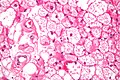

Hibernoma. H&E stain.

LM large polygonal/oval cells with central & small nucleus; nucleoli typically prominent; cytoplasm multivacuolated, oval, eosinophilic, granular

LM DDx reaction to silicone implant

• Large polygonal/oval cells:

• Nucleus - central & small.[6]

• Nucleoli typically prominent.[7]

• Cytoplasm - multivacuolated, oval, eosinophilic, granular.

• +/-Prominent blood vessels, central.[8]